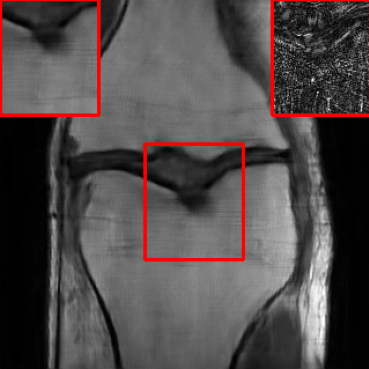

Performance on the Stanford FSE Dataset: We also performed image reconstructions with the Stanford multi-coil FSE dataset, which is a smaller dataset. We used same settings for the networks and training as in Section IV-A. Table III shows that LONDN-MRI significantly outperforms the globally learned MoDL network at both 4x and 8x acceleration. This indicates benefits for the proposed framework for smaller, more diverse datasets. Figs. 7 and 8 display visual comparisons that show the LONDN-MRI scheme recovering sharper features than the globally learned network.

| Ground Truth | Initial | Global | LONDN-MRI | LONDN-MRI | Oracle |

| (1 iteration) | (2 iterations) | ||||

![]() |

| PSNR = dB | PSNR = 19.41 dB | PSNR = 26.52 dB | PSNR = 27.76 dB | PSNR = 27.85 dB | PSNR = 27.92 dB |